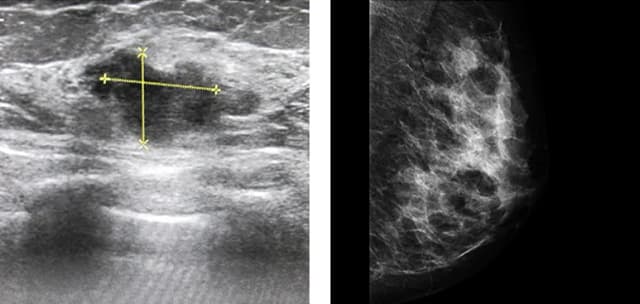

Tag klasyfikacja bi-rads